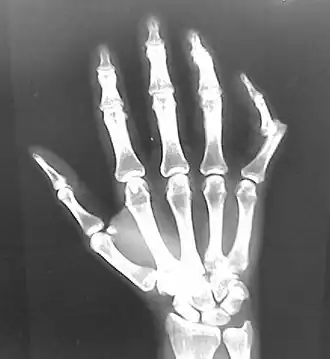

• Finger

• Interphalangeal (IP) or metacarpophalangeal (MCP) joint dislocations[41]

• In the United States, men are most likely to sustain a finger dislocation with an incidence rate of 17.8 per 100,000 person-years.[42] Women have an incidence rate of 4.65 per 100,000 person-years.[42] The average age group that sustain a finger dislocation are between 15 and 19 years old.[42]

• The most common dislocations are in the proximal interphalangeal (PIP) joints.[8]